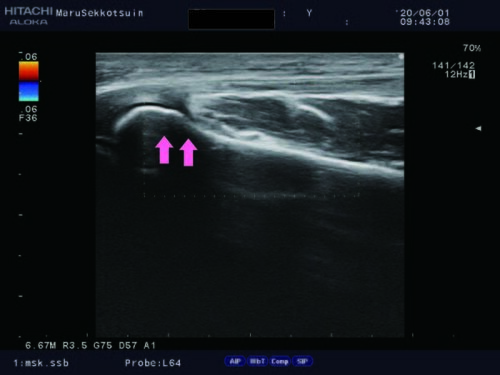

転んで手を突いて「橈骨頭骨折」

橈骨頭骨折.jpg